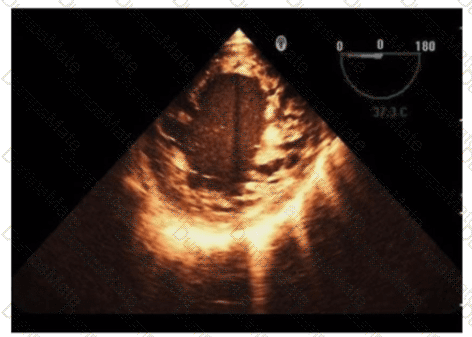

Questions 18

Which coronary artery is identified by the arrow on this image?

AE-Adult-Echocardiography Question 18

Options:

A.

Right

B.

Left main

C.

Circumflex

D.

Left anterior descending